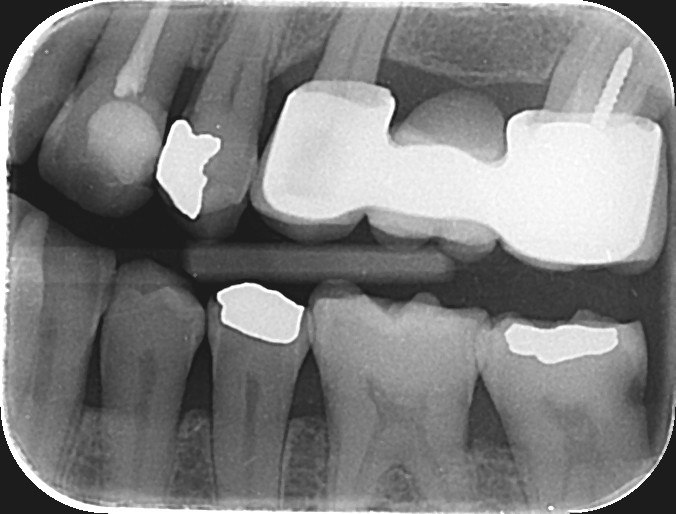

3. What condition can be detected in mesial surface of the tooth # 2.5?

4. What is the condition in the distal surface of the tooth # 3.4?

5. What is the condition in the distal surface of the tooth # 3.3?

6. What is the condition on dista surface of the tooth # 3.7?